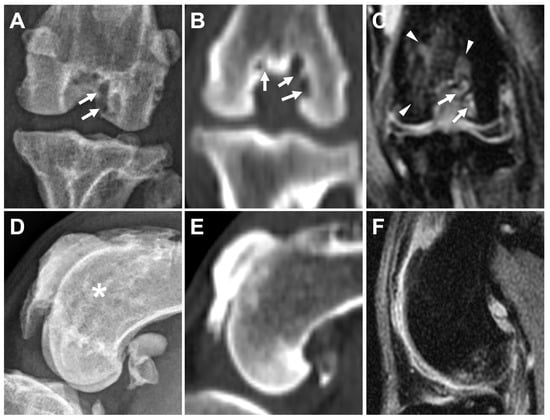

3.2.1. Osteophytes/Enthesophytes

3.2.2. Ligament/Tendon Lesions

3.2.4. Subchondral Bone Lesions

3.2.5. Meniscal and Cartilage Lesions